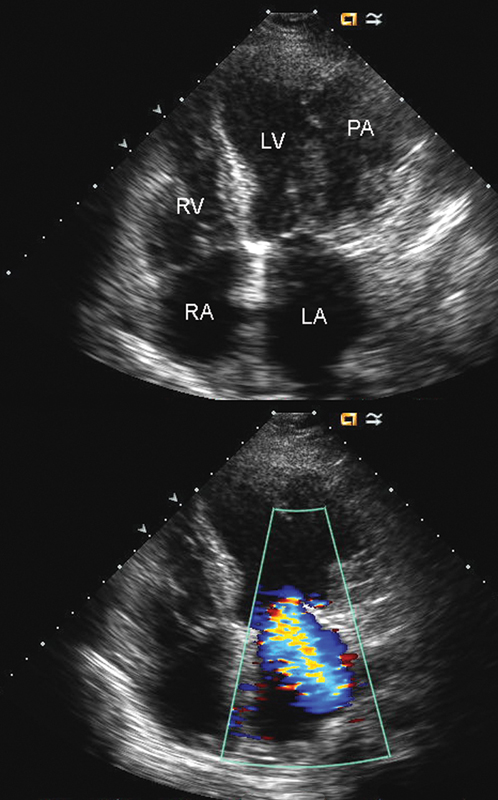

فحوصات تشخيصية لبعض امراض القلب والشرايين التاجية